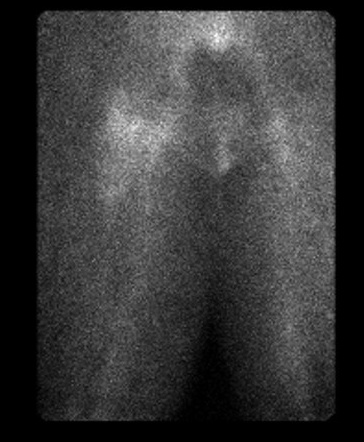

Quiescent bone scan

Infected THA on blood flow and blood pool

Infected THA on delayed phase